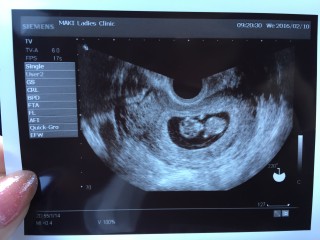

9週から重症妊娠悪阻で入院中。 赤ちゃんは順調でした! 手足もへその緒も見れて感激! 点滴で絶飲食…辛いけど 赤ちゃんの為にも頑張ります! CRL:35.0mm

人っぽくなってきたwww 心拍も確認できて元気! 一緒に頑張ろうね。 お姉ちゃんお兄ちゃんも待ってるよ!

今日は初めて心音を聞くことができました。重い悪阻と切迫流産であったため、心音を聞けた瞬間に内診室で号泣!悪阻辛いけど、頑張れます。